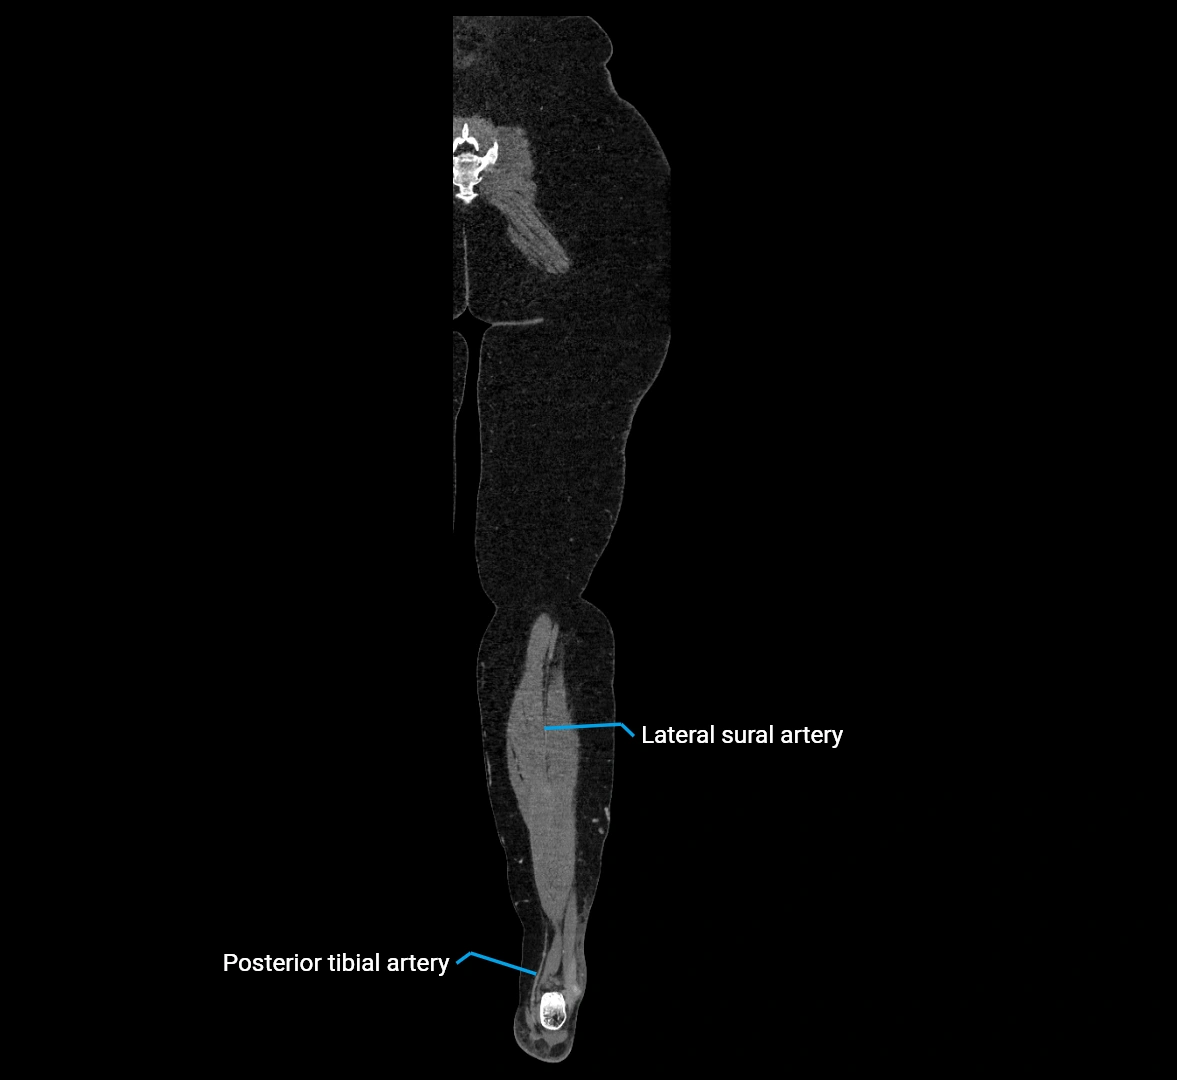

CT images

image

CT Appearance

Non-contrast CT:

• Appears as a tubular soft tissue structure anterior to vertebral bodies

• Calcified atherosclerotic plaques appear as hyperdense foci along the wall

• Useful for screening abdominal aortic aneurysm (AAA) size and mural calcification

Contrast-enhanced CT (CTA):

• Gold standard for abdominal aortic imaging

• Provides excellent detail of lumen, wall, aneurysm, thrombus, and branch vessels

• Multiplanar and 3D reconstructions help in aneurysm measurement, stent graft planning, and dissection evaluation

• Detects acute rupture, traumatic injury, or occlusion with high sensitivity